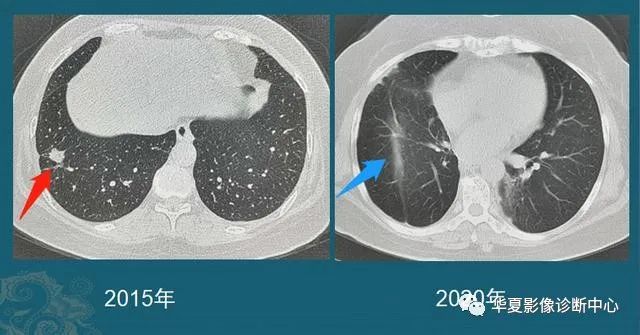

病例2

男性,75岁,体检发现左肺结节,2.9 cm,左肺下叶切除5年(病理类型不详,在外院手术,家属只记得是肺癌,不能描述具体类型,看肿瘤形态,鳞癌、腺癌都有可能):

图9

病例3

女性,61岁,胸闷一周查出肺癌,3.5 cm,有分叶、胸膜牵拉,并且已经侵犯局部脏层胸膜,手术后病理是肺腺癌:

图10受益于网络时代的交流便利,很多读者朋友喜欢研究肺结节的诊断和治疗,希望今天这批病例分享对大家有帮助。